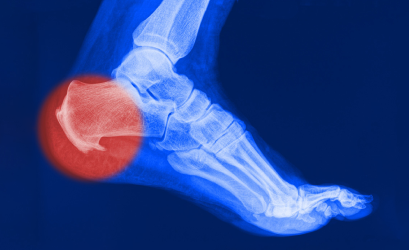

Активность человека снижается, воспалительный процесс затухает и на месте поврежденных волокон возникают костные разрастания, которые видны на рентгенограмме и имеют характерный вид «шпоры».

Вот поэтому это заболевание и называют «пяточной шпорой», хотя сама «шпора» является уже результатом длительно протекающего плантарного фасциита.

Рентгенография пяточной области необходима для исключения перелома, если в анамнезе есть указания на травму. На ранних этапах формирования пяточная шпора на рентгенограмме не визуализируется.